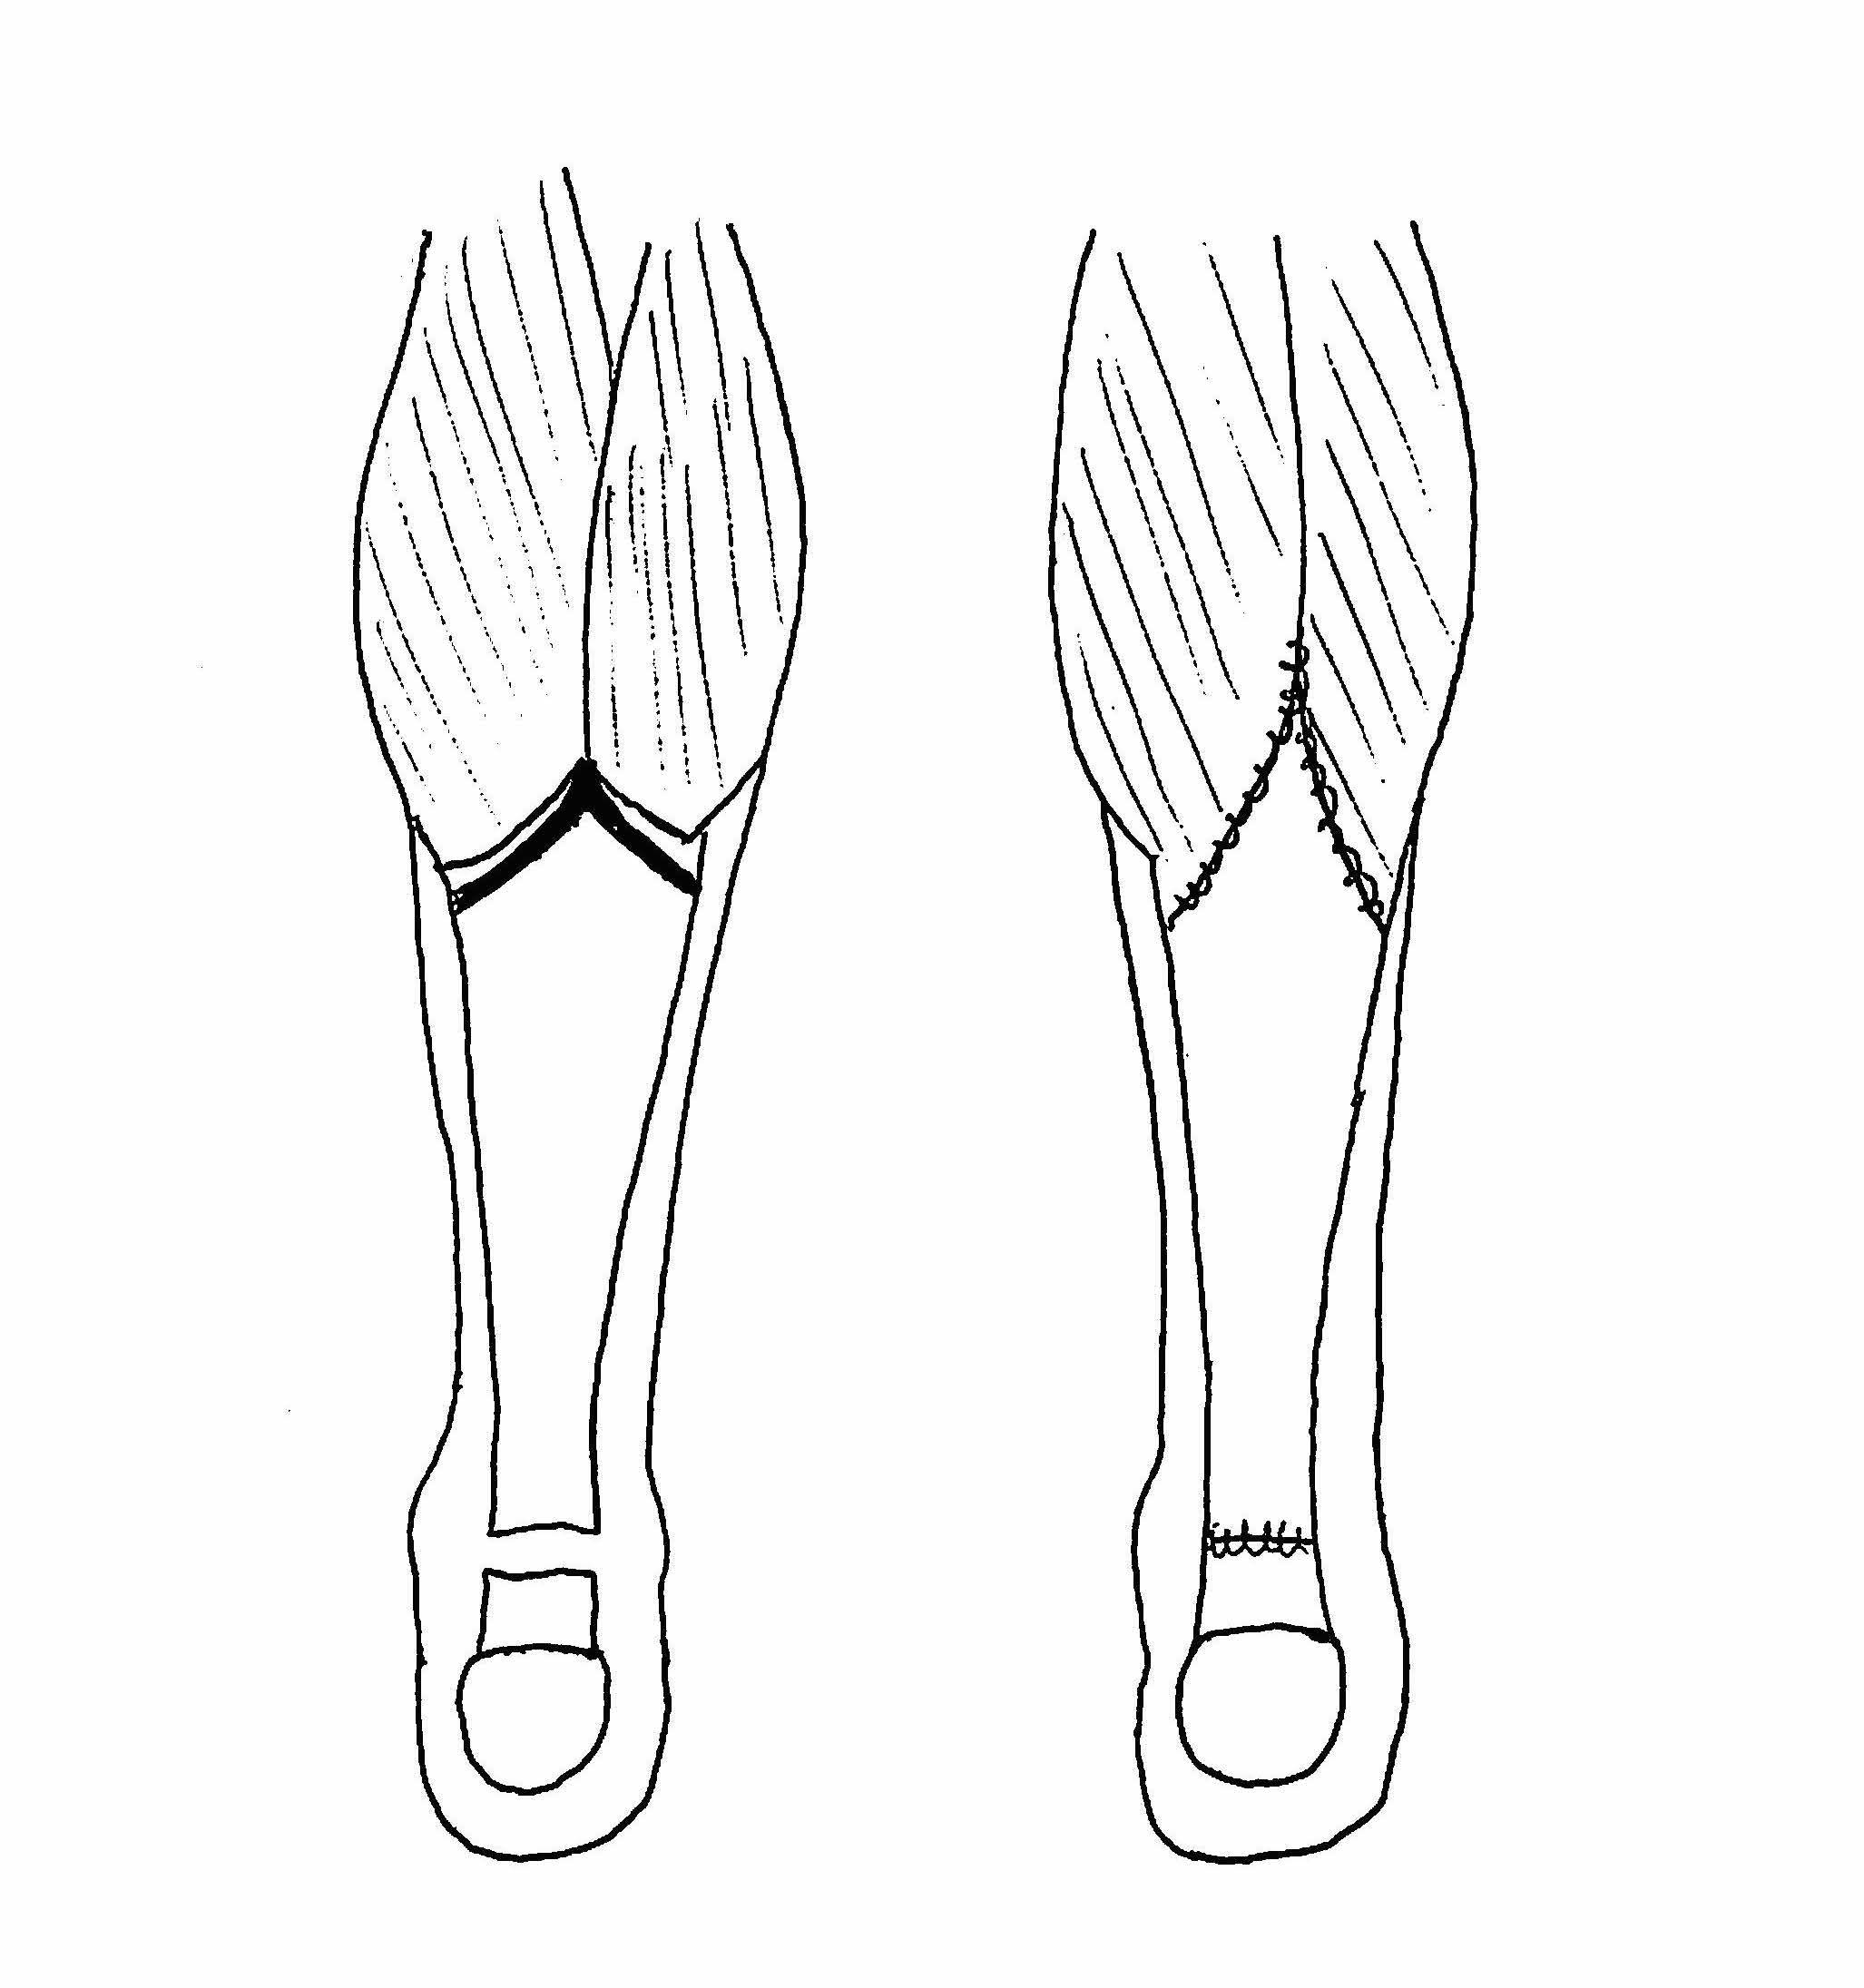

VY lengthening

Technique

Vumedi VY lengthening + FHL transfer video